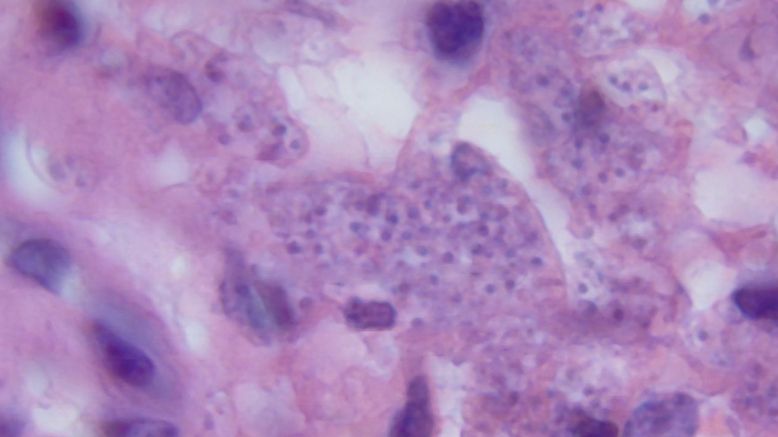

Badanie pozwala bez problemu zdiagnozować postać skórną lub skórno-śluzówkową. W rozpoznaniu i diagnostyce leiszmaniozy pomocne jest również barwienie metodą Giemsy. Nieco rzadziej stosowane są też badania serologiczne. Leiszmanię trzewną diagnozuje się na podstawie badania histopatologicznego. U pacjentów przeprowadzona zostaje biopsja śledziony, wątroby lub szpiku.